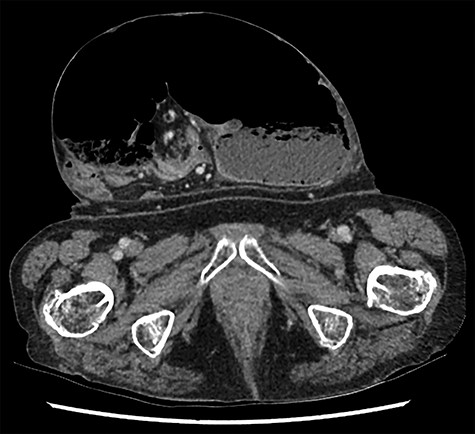

Caecal volvulus, showing distended caecum within ventral hernia showing mesenteric swirling (axial).

A clinical diagnosis of bowel obstruction was made; she underwent a CT abdomen/pelvis with contrast, which demonstrated a large bowel obstruction within the hernia not caused by the hernial defect but thought likely due to volvulus of the caecum (Figs. 1 and 2).